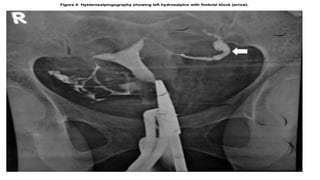

Hysterosalpingraphy

Tubal findings Endometrial findings

• Occlusion

• Hydrosaplinx

• Beading

• Tobacco pouch

• Maltese cross appearance

• calcification

• Synechiae

• Irregular contour

In known cases or in circumstances in

which genital TB is highly suspected,

HSG should be avoided because of

risk of activation.

Tobacco- pouch appearance

Tube is enlarged and distended,

ostium remain patent with

recognizable everted fimbriae